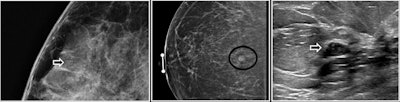

Flat epithelial atypia is a type of benign breast lesion that often presents as microcalcifications. Although rare, FEA is becoming increasingly diagnosed at core needle biopsy due to the improved ability of breast imaging to detect microcalcifications.